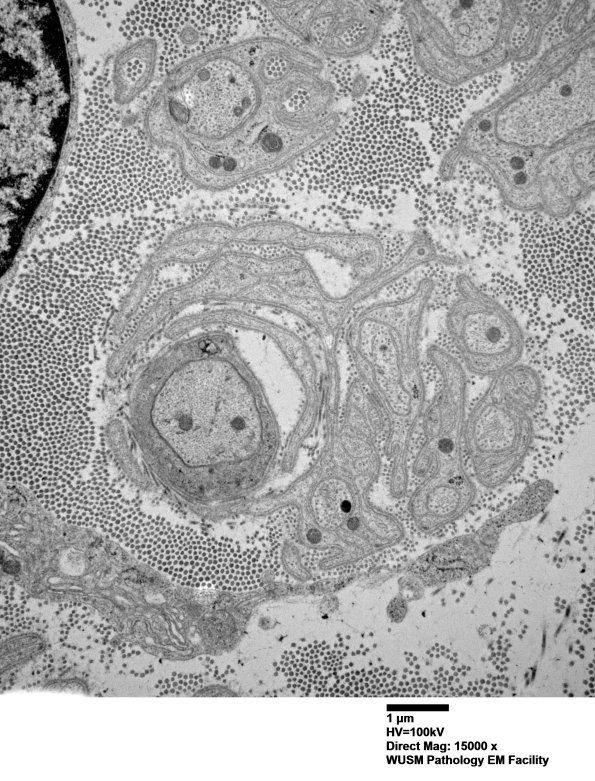

An example of demyelination of a small axon; note the adjacent smaller unmyelinated axons. (electron micrograph)